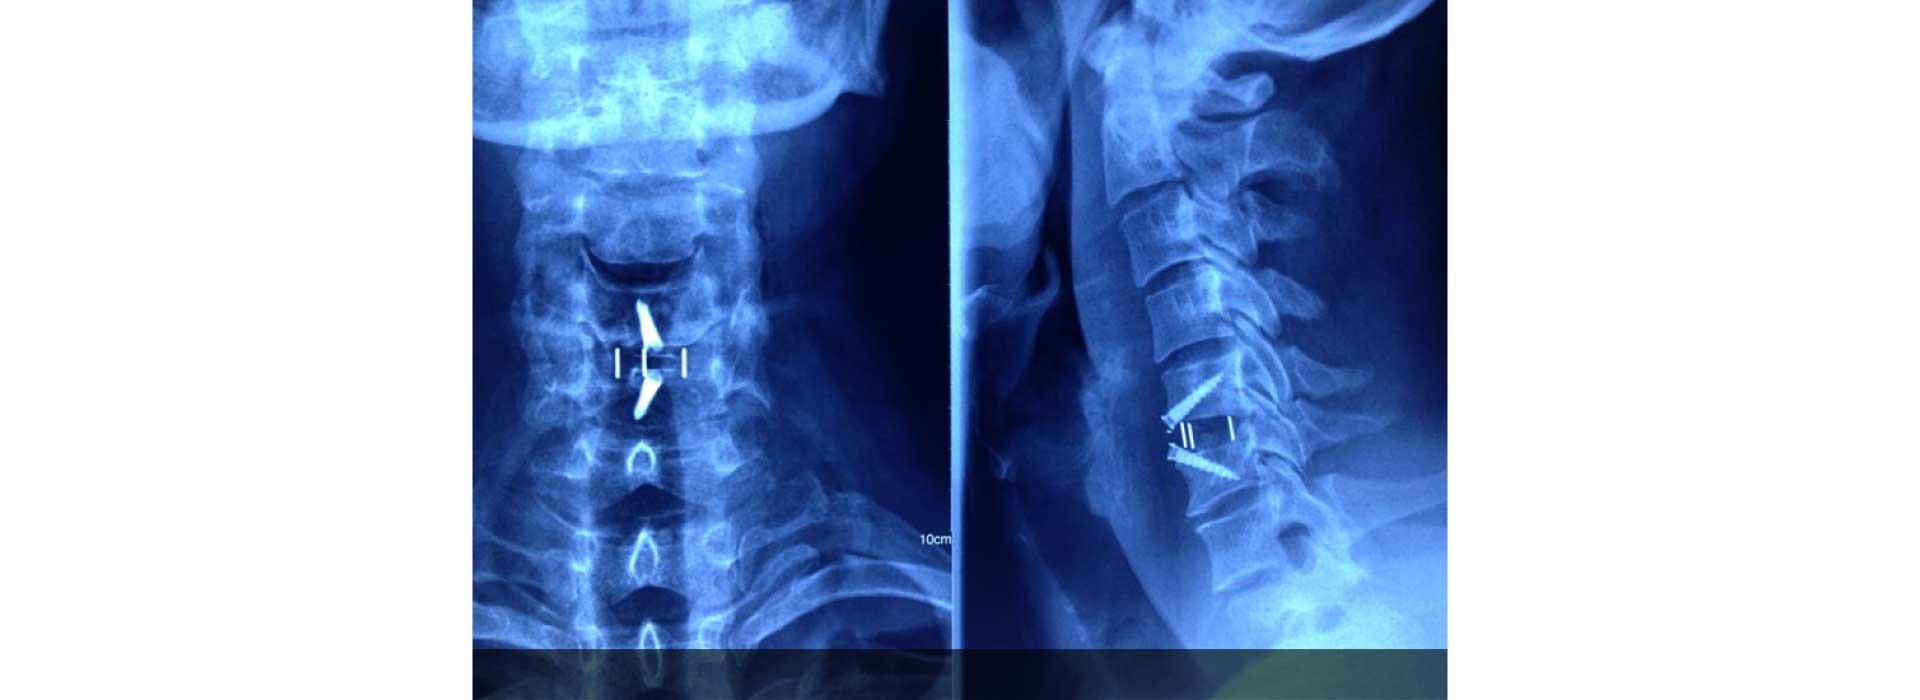

All kind of simple and complex surgery for cervical, dorsal and lumbar spine